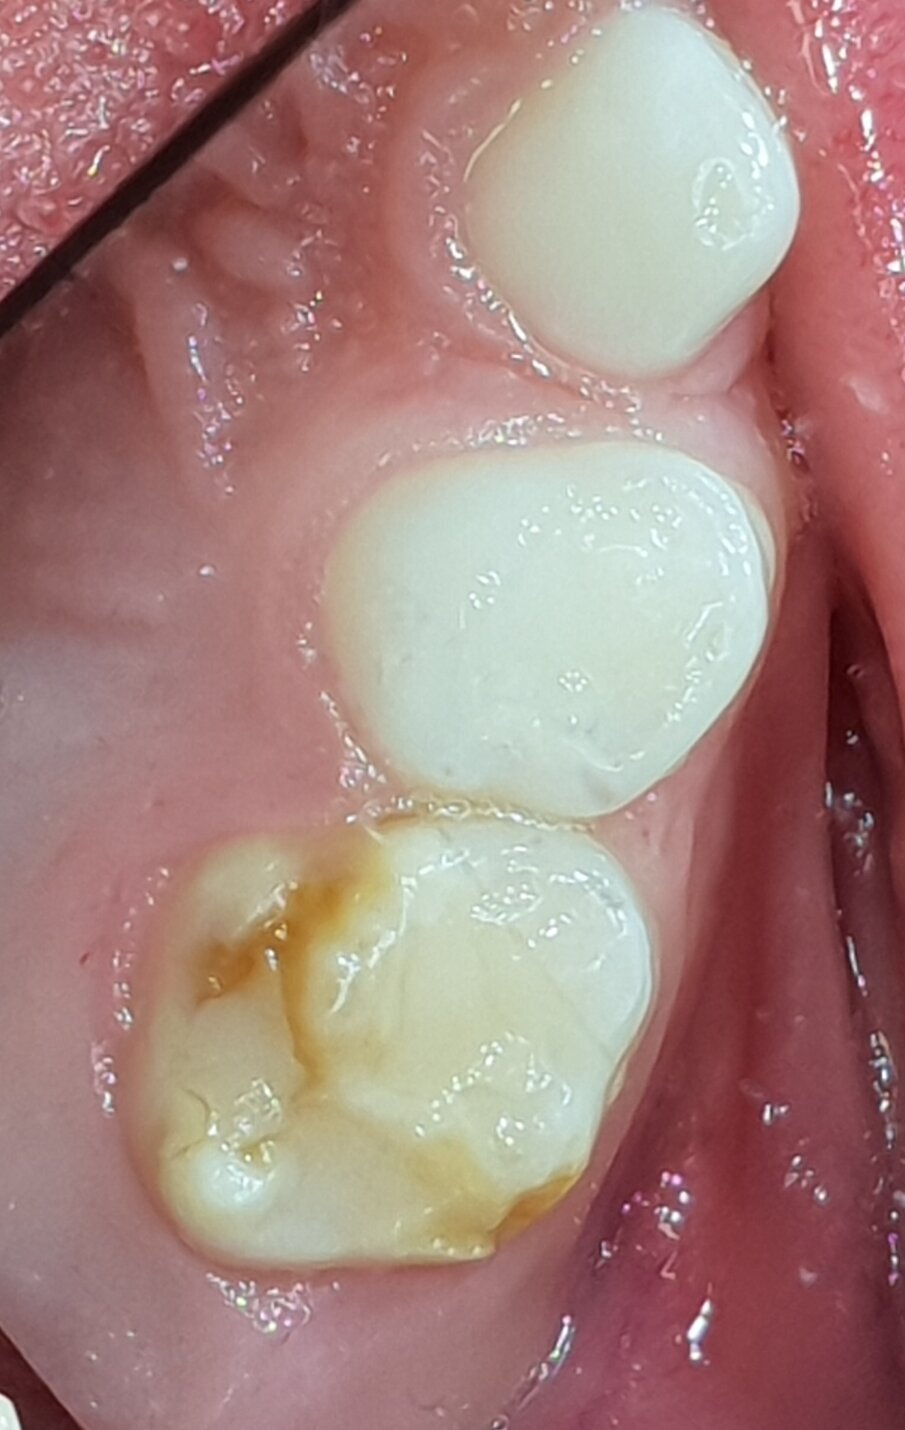

Afbeelding 4a. Resultaat ART in plaats van narcosebehandeling na drie jaar.

Afbeelding 4b. Resultaat SMART-methode in plaats van narcosebehandeling na drie jaar.

Een jong kind werd in 2016 verwezen voor behandeling met een kroon onder narcose van de 55. Ik zag daar geen reden toe en behandelde de molaar volgens de ART-methode. Bij een ander kind met dezelfde indicatie paste ik SMART toe: SDF in combinatie met ART. Bij evaluatie na 3 jaar was het resultaat bij beiden bevredigend (afb. 4a-b).